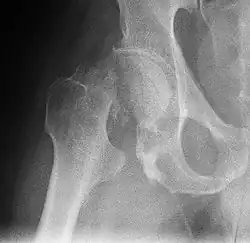

Mediale Schenkelhalsfraktur ohne Dislokation -

Im Vergleich dazu ein gesundes Hüftgelenk